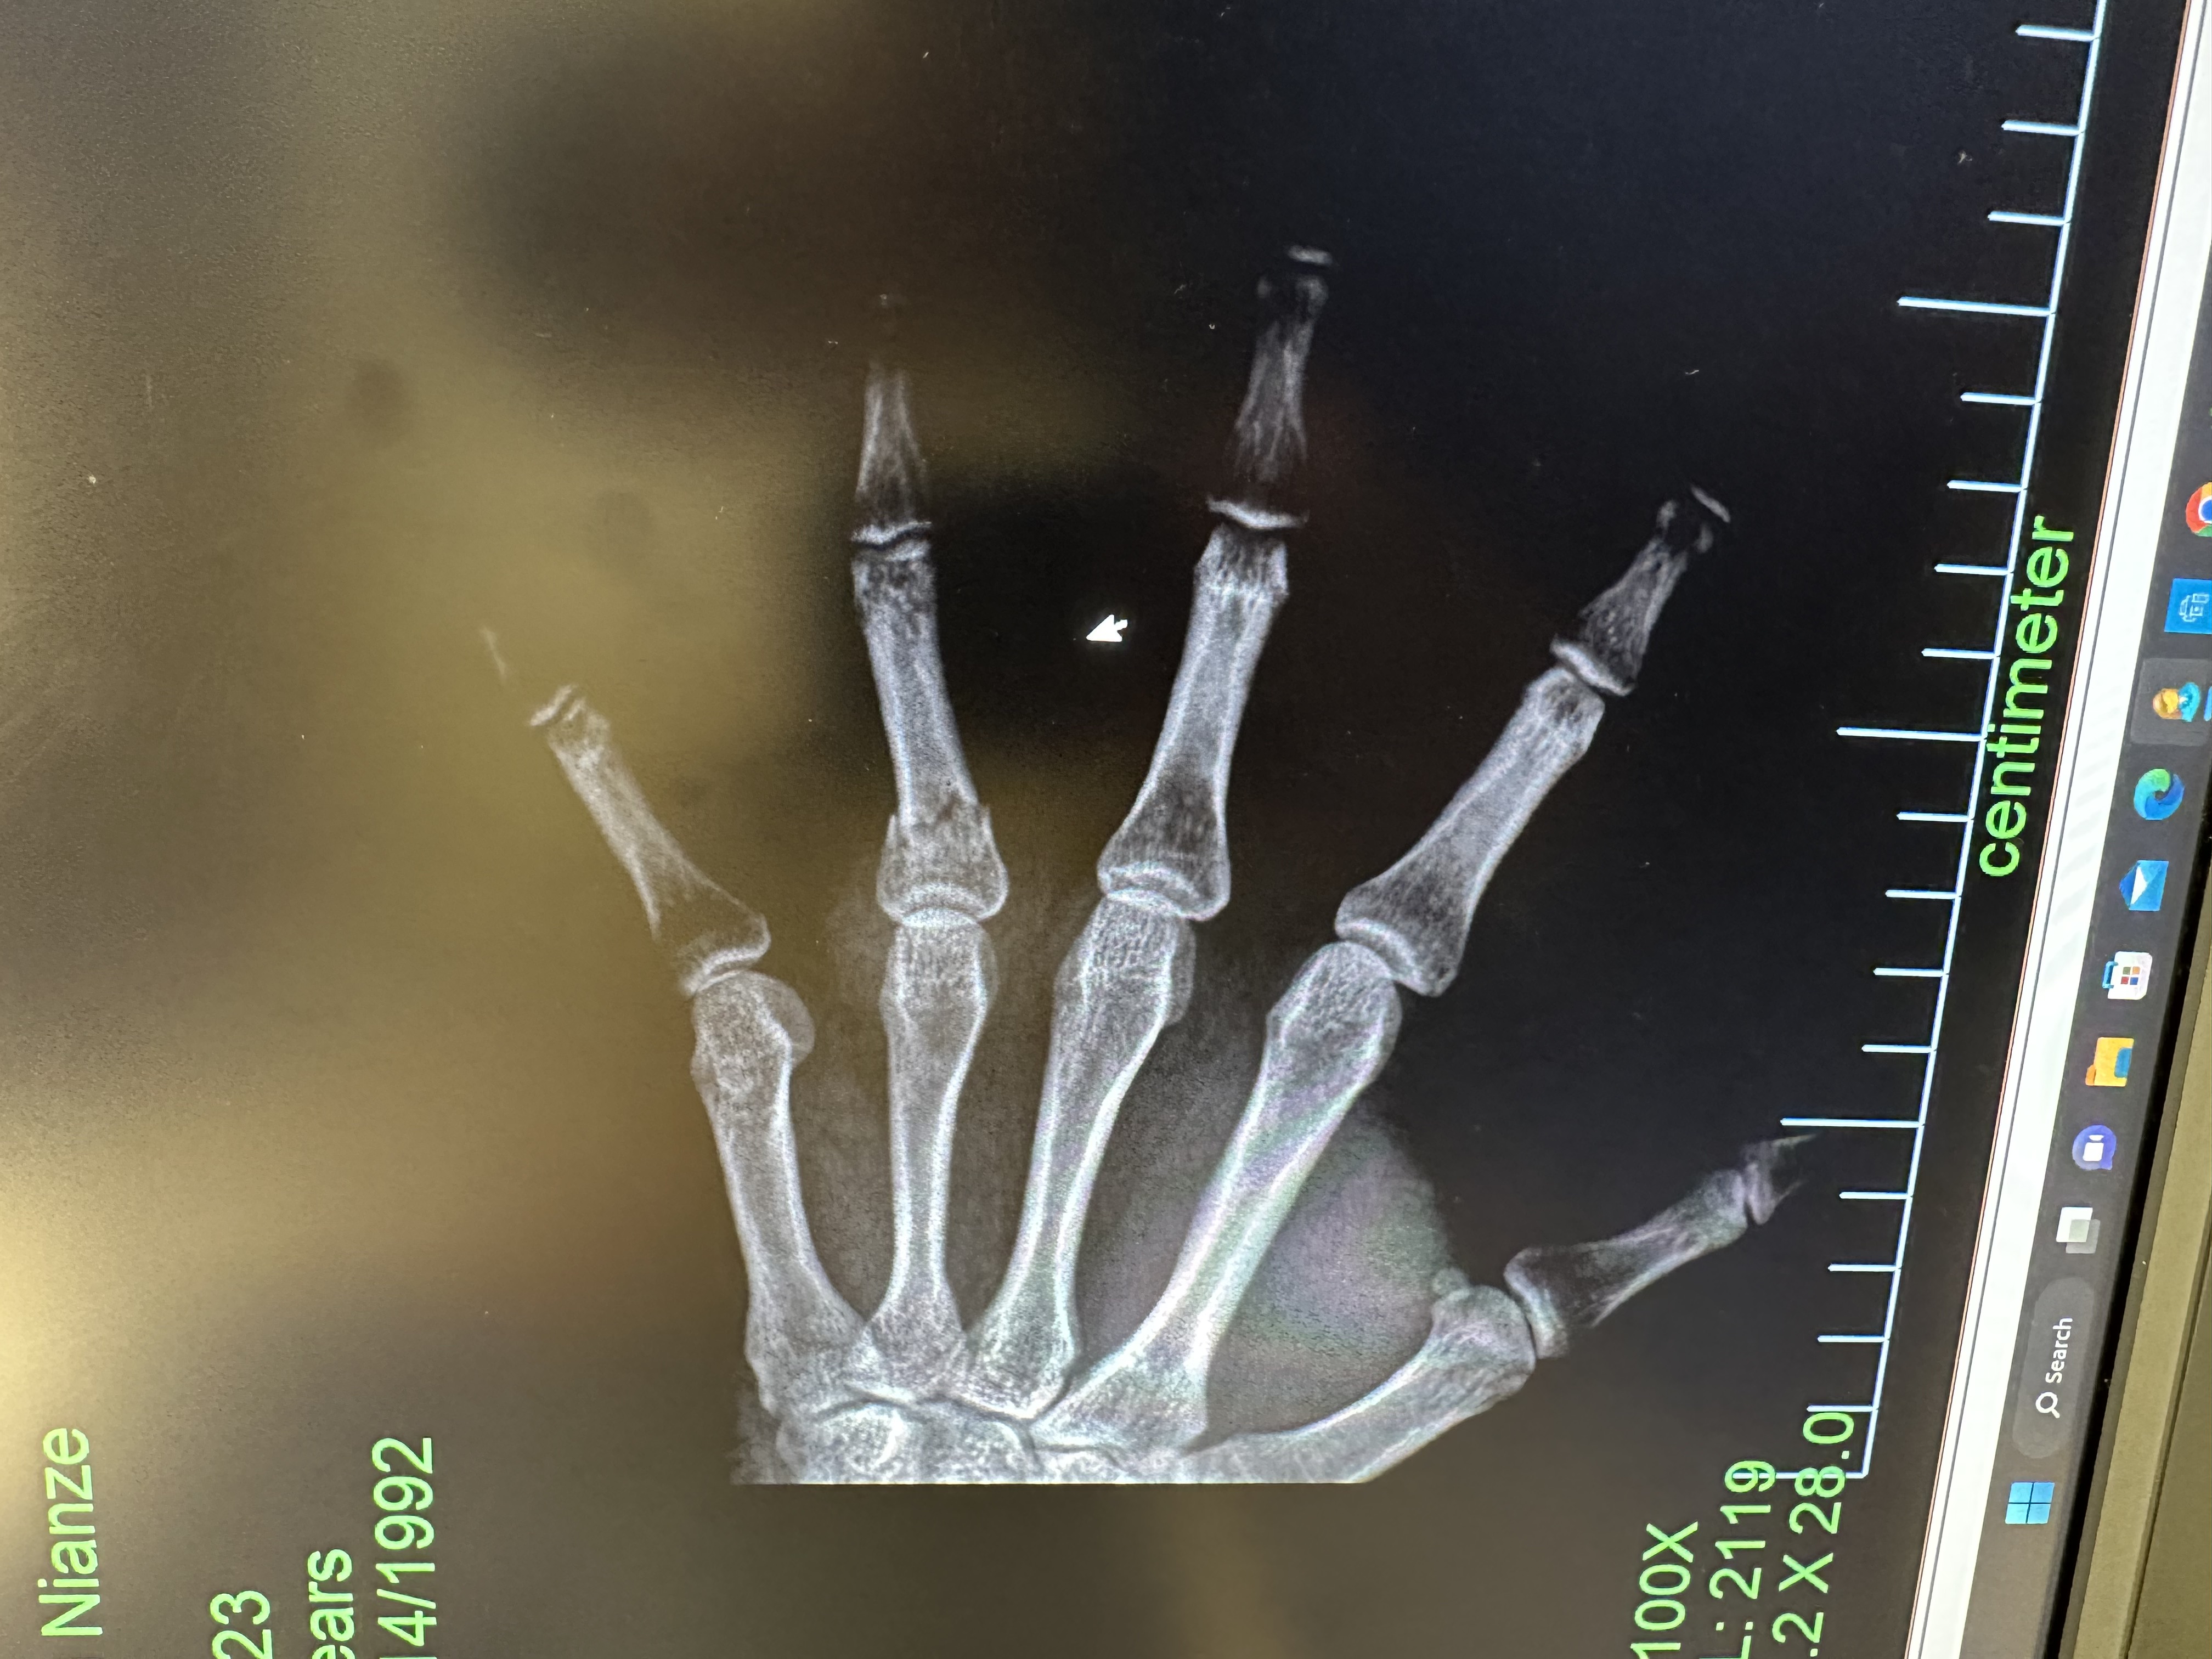

Ironically I didn’t get hurt during a 6-week ski/snowboarding trip in SLC, but broke my hand climbing stairs on the first day back in the NYC office 🤣.

A transverse fracture shows at the 4th proximal phalanx of the right hand.: